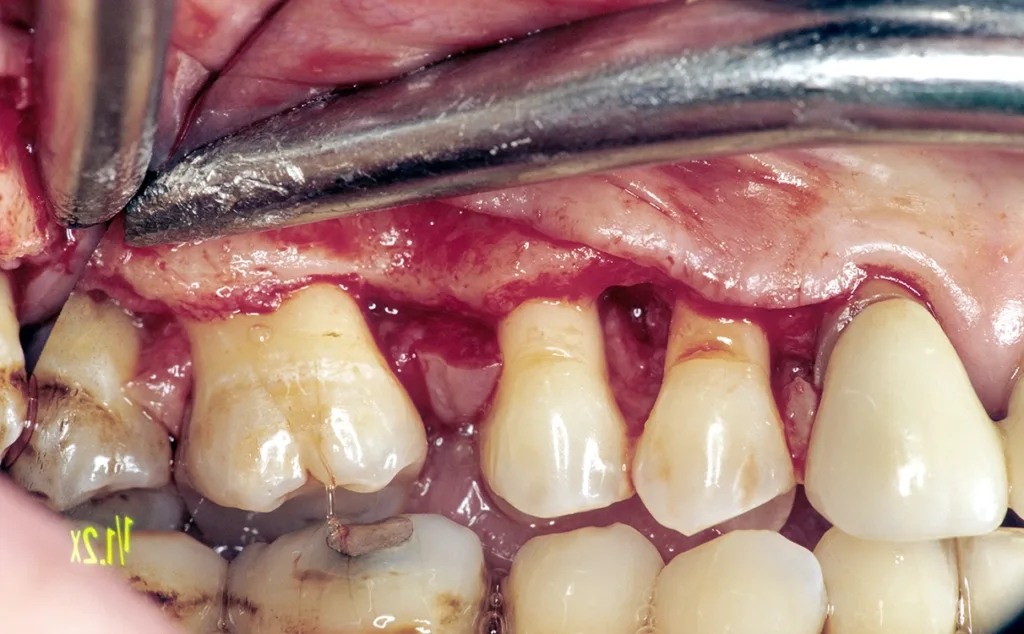

Daraus resultiert ein zweizeitiges Vorgehen mit (i) Entfernung prognostisch unsicherer Zähne, (ii) parodontaler Zieltherapie zur Sicherung des Restzahnbestandes, ergänzt durch (iii) mikrochirurgische Revision tiefer Resttaschen vor Implantation zum weiteren Entzündungsschutz (Abb. 3 und 4). Die Implantatplanung bleibt vorläufig. Ein definitiver Kostenvoranschlag wird erst nach funktioneller Entlastung und digitaler Beurteilung der Implantatknochenanatomie erstellt.

Weichgewebsschutz (Volumen)

Aufgrund bestehender Knochendefizite nach Extraktion, Parodontitis oder bei Fehlfunktion sind die Voraussetzungen an eine ausreichend breite Zone an keratinisierter Gingiva um Implantate häufig nicht ideal [14]. Zur Planung und Sicherung des chirurgischen Vorgehens sollten bereits bei der Erstellung des KVs die GOÄ-Positionen ä 2382, ä2386 und ä2677 mit den entsprechenden GOZ-Zuschlägen berücksichtigt werden. Folgendes Vorgehen hat sich bewährt:

- Bei ortsständiger Implantation Verbreiterung der periimplantären Gingiva durch leicht oralwärts verlagerte Inzision (reicht meist aus).

- Bei lateraler Augmentation ist eine Verbreiterung aufgrund der Lappenmobilisation zur Defektdeckung absehbar. In der Einheilungsphase vor Freilegung separater Behandlungstermin mit Vestibulumplastik und freier Schleimhauttransplantation (Gaumen) (Abb. 17 bis 19).